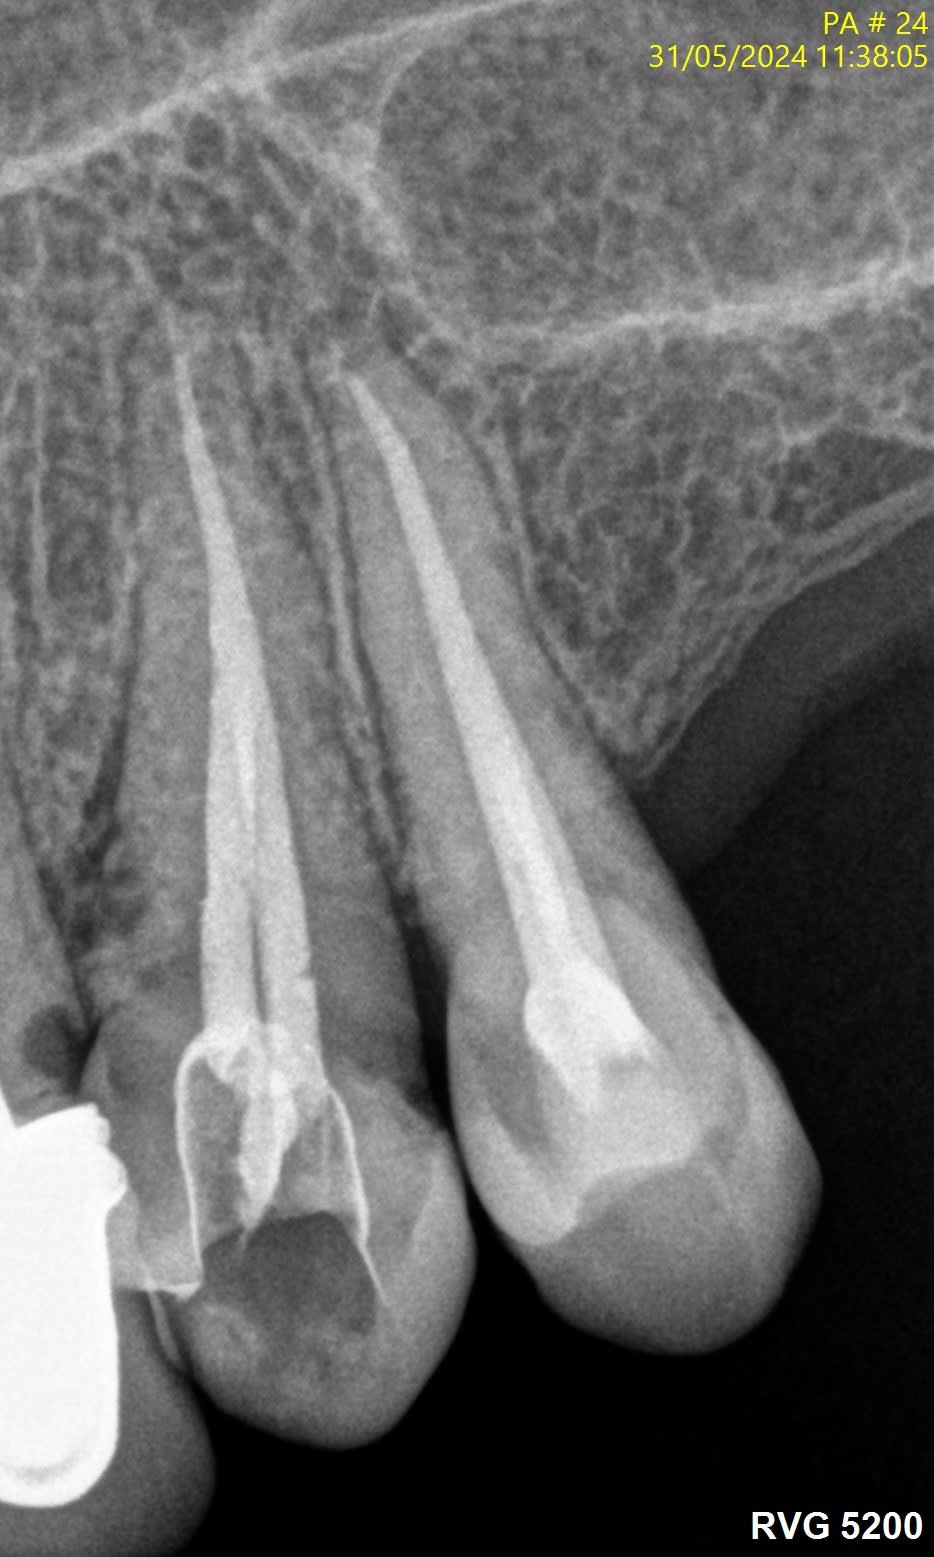

Voici quelques radio pour illustrer...

J’ai l’impression que sur les radios que tu montres il y a des fractures verticales.

La 24 et la 25, t'aurais carrément dû les virer...